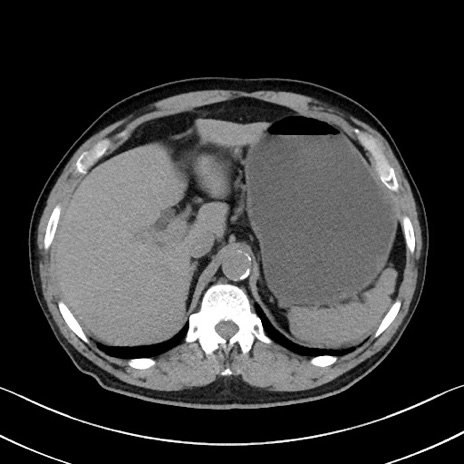

症例35(横断像)

冠状断像

【症例】70歳代 男性

【主訴】腹部膨満、嘔吐

【現病歴】昨日より腹部膨満感出現。本日増悪し、仙痛出現。嘔吐あり、受診。

【既往歴】糖尿病、胆摘後

【身体所見】BP 149/80mmHg、HR 74/min、BT 35.9℃、腹部:膨満、軟、圧痛なし。腸雑音減弱あり。上腹部正中切開瘢痕あり。

【データ】WBC 13500、CRP 1.72